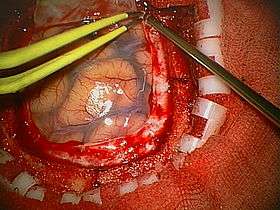

A craniotomy is a surgical operation in which a bone flap is temporarily removed from the skull to access the brain. Craniotomies are often critical operations, performed on patients who are suffering from brain lesions or traumatic brain injury (TBI), and can also allow doctors to surgically implant deep brain stimulators for the treatment of Parkinson's disease, epilepsy, and cerebellar tremor.

Human craniotomy is usually performed under general anesthesia but can be also done with the patient awake using a local anaesthetic; the procedure, typically, does not involve significant discomfort for the patient. In general, a craniotomy will be preceded by an MRI scan which provides an image of the brain that the surgeon uses to plan the precise location for bone removal and the appropriate angle of access to the relevant brain areas. The amount of skull that needs to be removed depends on the type of surgery being performed. The bone flap is then replaced using titanium plates and screws or another form of fixation (wire, suture, etc.).